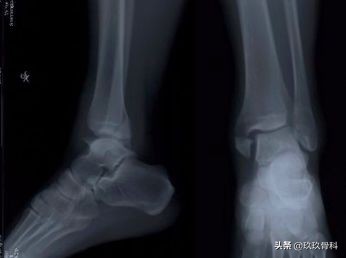

踝的骨折▲▲▲

- X线 踝关节正侧位(必要时应加照踝穴位)

诊断:体检—疼痛肿胀压痛的部位在踝的前上方;X线—踝内旋20°正位